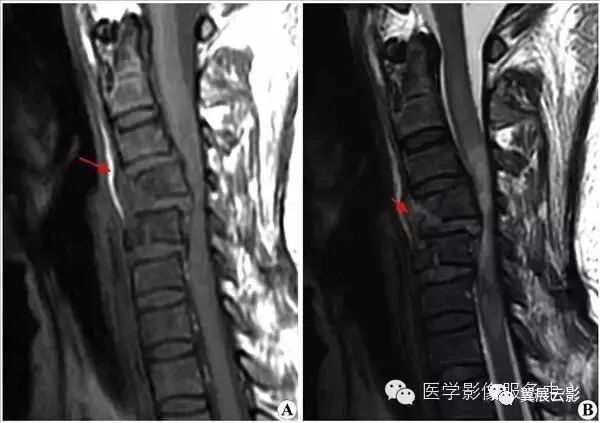

【MRI图片】:

【影像表现】:T2WI(B)C4、C5椎体骨折,C4椎体后滑脱,相应水平脊髓受压变细,信号增高;T1WI(A)示脊髓变细,信号减低。

【影像诊断】:颈段脊髓损伤。